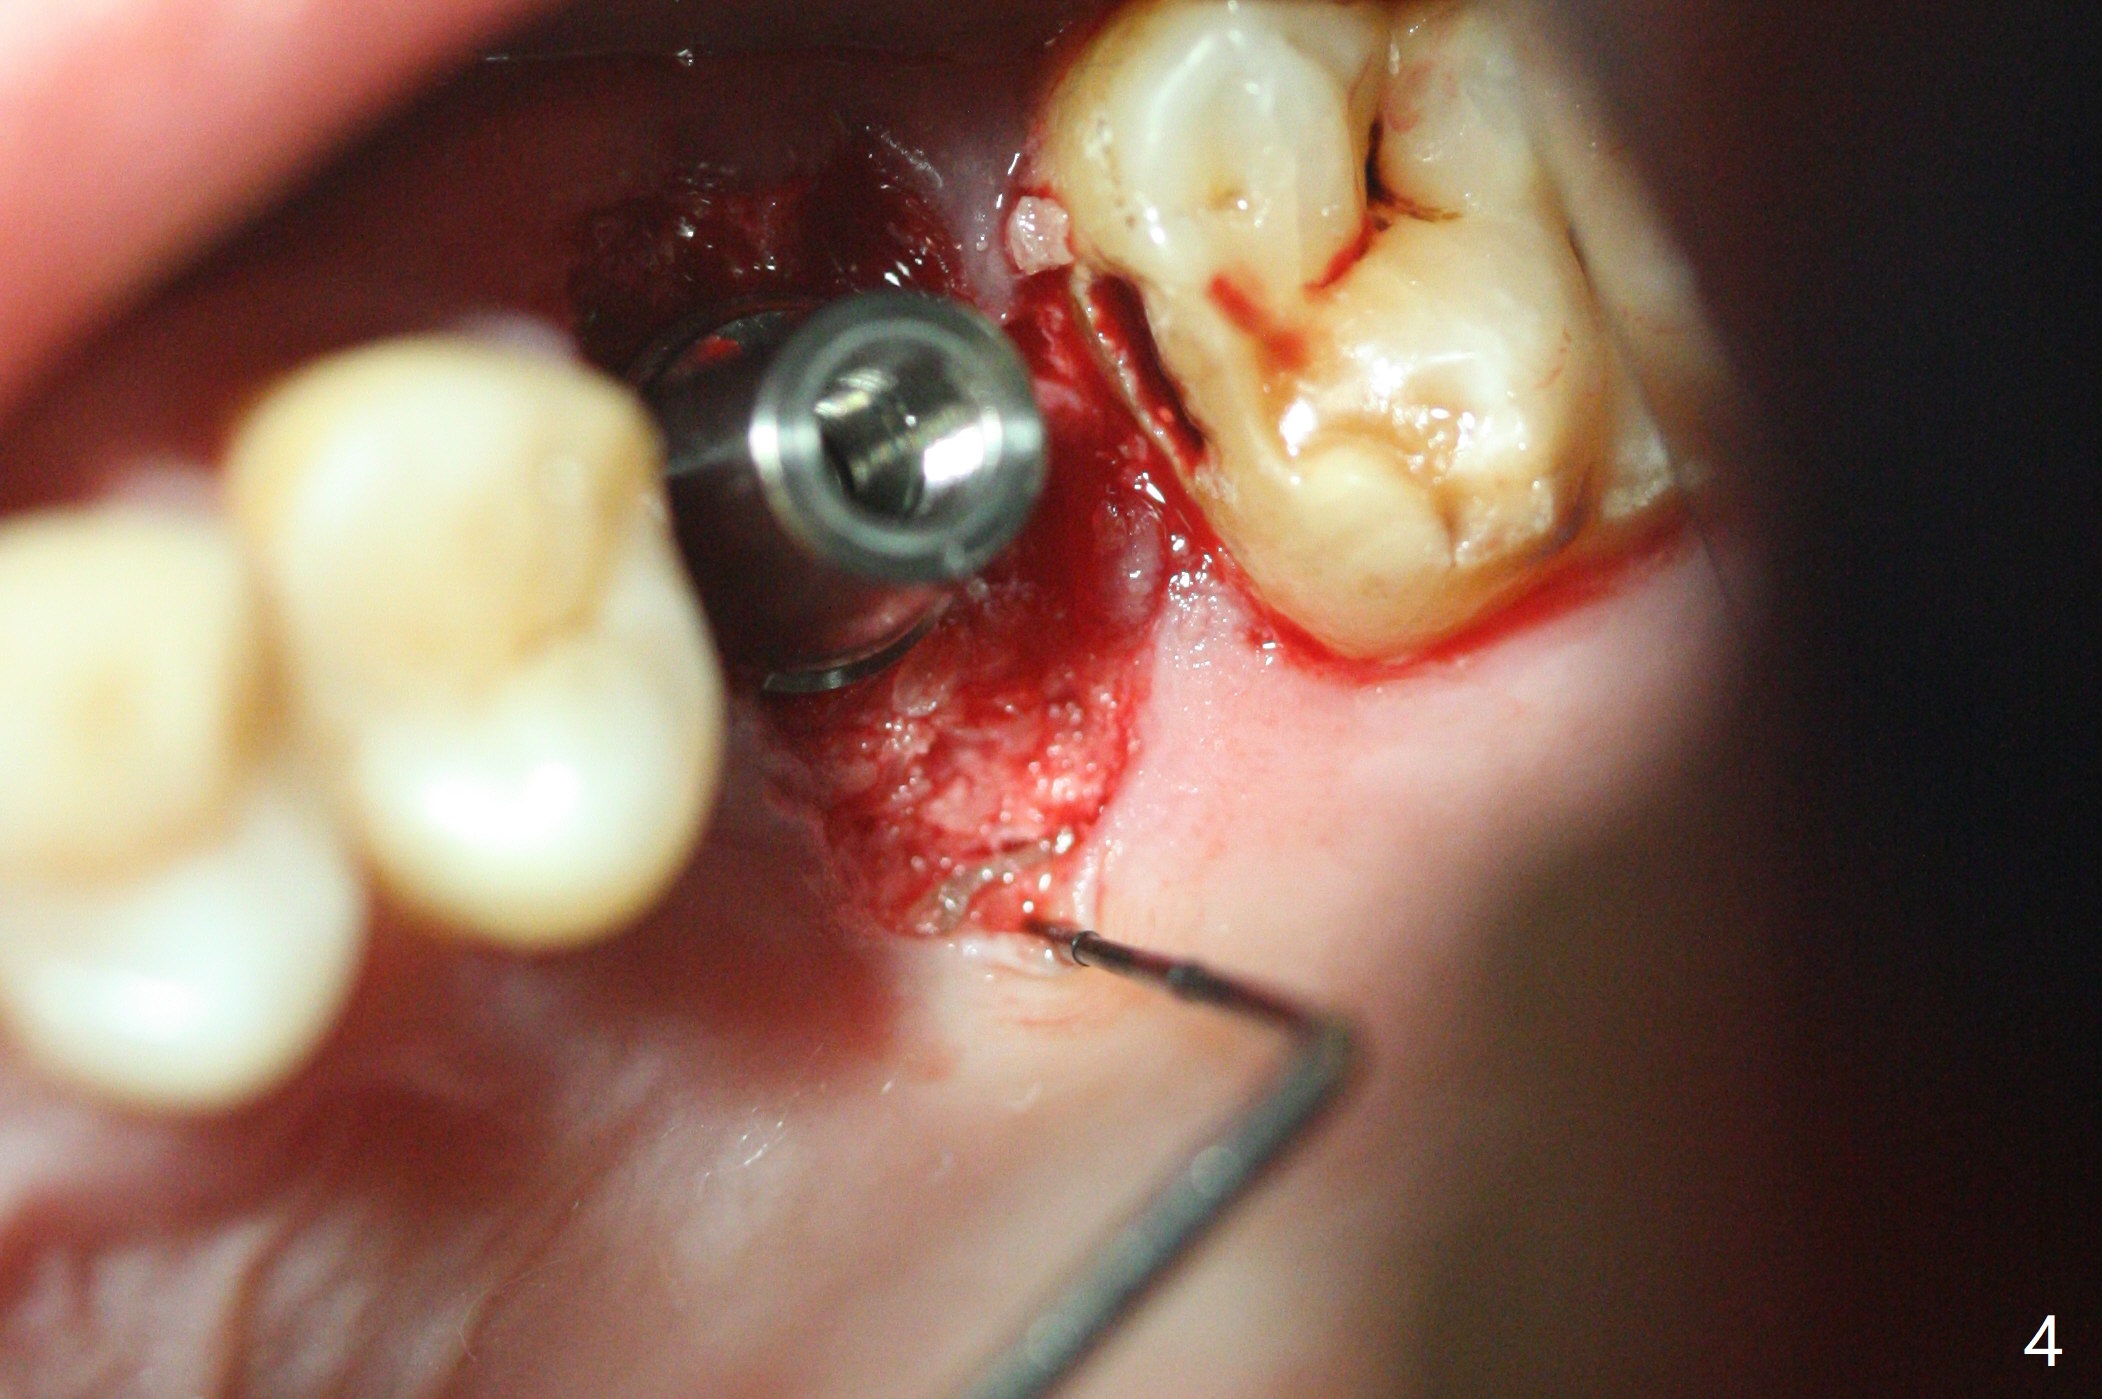

With modification of drill sequence in the last 3 steps (4.5x7.3, 4.0x8.5 and 3.5x10 mm drills) at #14 and sinus lift (Fig.1), a 5x9 mm implant is placed with ~ 50 Ncm following back up twice. Sticky bone mixed with autogenous bone (Fig.1,2 white *) is placed in the sockets before and after placement of a 6.5x5.7(2) mm abutment. Since the palatal gingival margin is recessive (Fig.3 ^), a palatal socket shield retains to prevent further recession (Fig.4 in the end of periodontal probe). Because the margin of the abutment is low, it changes to one with longer cuff (Fig.5). An immediate provisional is fabricated (Fig.6,7 P). The bone graft is indistinguishable from the original alveolus 9 months postop (Fig.8 *). The palatal socket shield is exposed 10 months postop (Fig.9 <). Since the implant is intentionally placed buccal; the sheath is not essential.